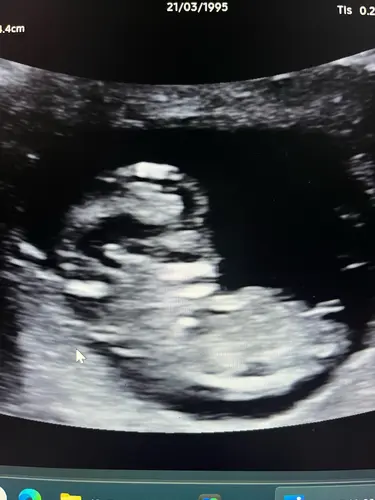

Hoi hoi, ziet iemand hier toevallig de nub theorie? Ik kom er zelf niet uit

Dat bovenste witte streepje rechts is volgens mij de nub. Staat in meisjes-stand maar dit hebben ze tot 12 weken bijna allemaal. Zie dat je 11 weken bent, misschien ben je net te vroeg